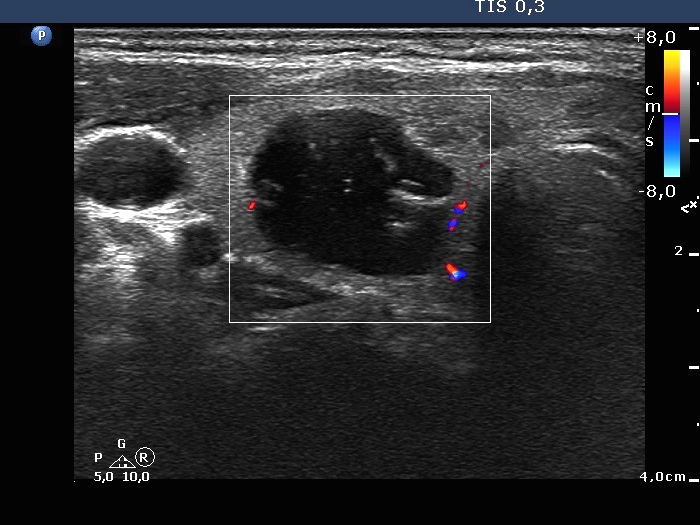

The composition of the nodule - case 142 (ultrasonographic picture 6)

Right lobe, longitudinal scan

Right lobe, transverse scan, color Doppler mode. The lesion is practically avascular.